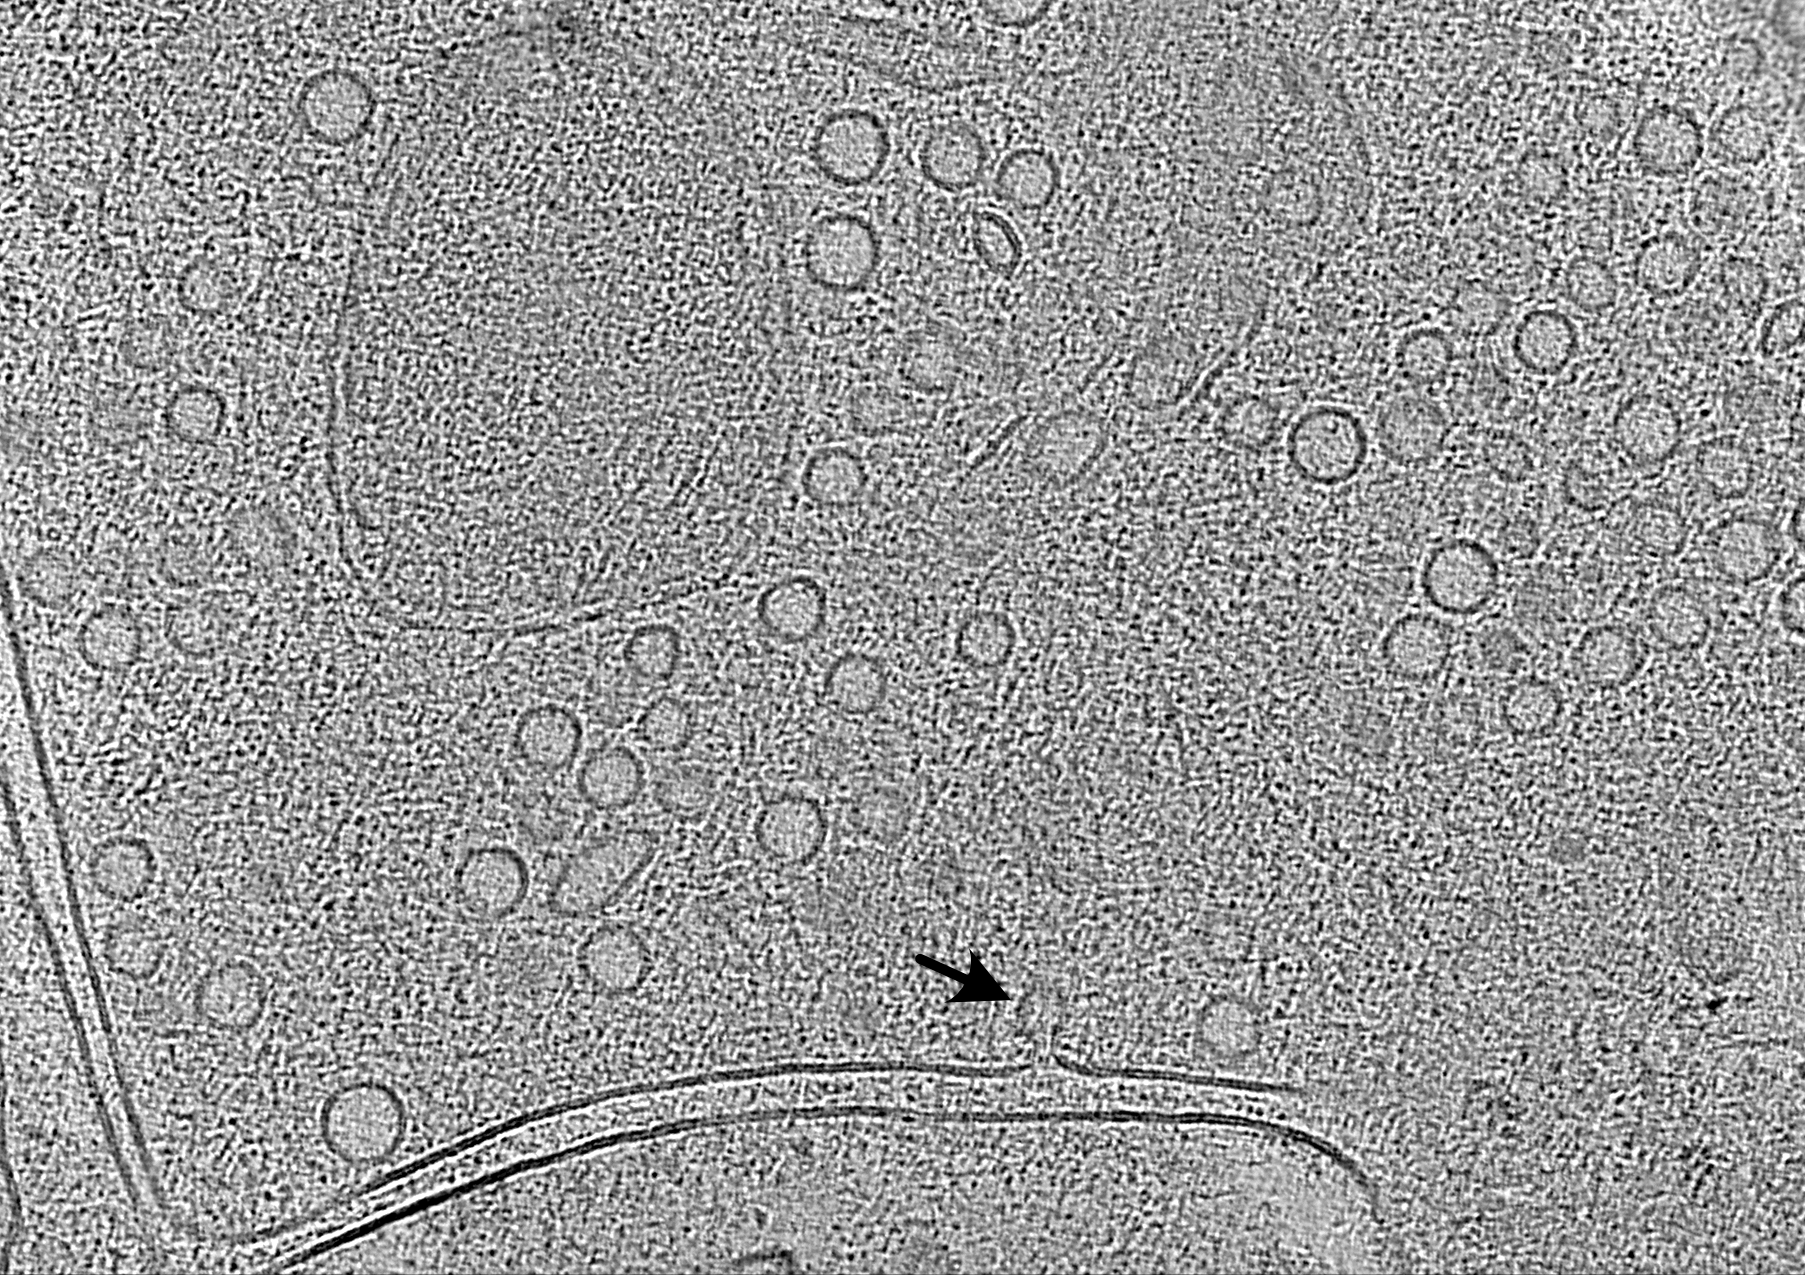

📸 A team from #CharitéBerlin & [@MDC_Berlin]( ) has observed synapses in action without disrupting them! The researchers have now microscopically captured the ultrashort moment when a neuron releases its neurotransmitters. 👉 P.S. The vesicle fusion process visualized by the team takes place millions of times a minute in the human brain.🤯 #CharitéPaper #science #research #brain #CharitéNeuro #biology #ScienceMastodon #medicine #photography

📸 Einem Team von #CharitéBerlin & [@MDC_Berlin]( ) ist es gelungen, Synapsen bei der Arbeit zuzusehen, ohne sie dabei zu stören! Die Forschenden haben den ultrakurzen Moment, in dem eine Nervenzelle ihre Neurotransmitter ausschüttet, nun mikroskopisch eingefangen. 👉 P.S. Die Fusion der Vesikel, die das Team visualisiert hat, findet in unseren Gehirnen jede Minute millionenfach statt. 🤯 #CharitéPaper #Wissenschaft #Forschung #Gehirn #CharitéNeuro #Biologie #ScienceMastodon